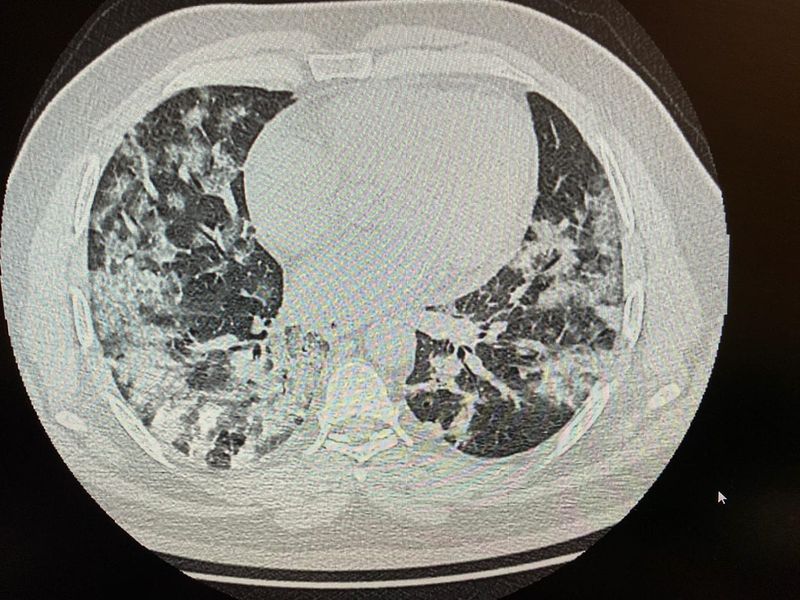

“Pacient în vârstă de 37 de ani, se prezintă la camera de gardă Floreasca pentru sdr subocluziv intestinal și subfebrilitate. CT-ul lui arată pneumonie interstițială. Are 65 saturație în oxigen.

“Imaginea CT e atât de sugestivă, saturația în oxigen nu mai spun, pacientul va pleca la lași sau în Medgidia, pe locuri eliberate în ATI. Acolo îl așteaptă Dumnezeu cu mila Lui. În București nu mai sunt locuri libere”, a mai scris Adina Cojocaru.